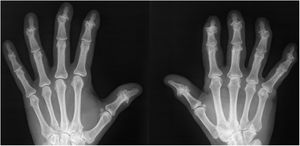

A 54-year-old woman presented with a 3-year history of pain and deformity of distal interphalangeal (DIP) joints in both hands. The pain was inflammatory in nature, with early morning stiffness of >1h. The patient's personal and family past medical history was unremarkable. She had partial response to various nonsteroidal anti-inflammatory drugs (NSAIDs). Physical examination revealed tenderness, swelling and decreased range of motion in the DIP joints. Laboratory evaluation revealed high ESR (39; range, 0–20mm/h) and CRP (18; range, 0–5mg/L) levels, with negative RF, anti-CCP and ANA. Based on clinical and laboratory findings referred to an inflammatory type pain due to the presence of joint inflammation. X-ray of the hands documented typical features of erosive hand osteoarthritis (OA) in DIP joints such as joint space narrowing, subchondral sclerosis, marginal osteophytes and erosions in the central portion of the joint giving “gull-wing sign” (Fig. 1). The patient had a high level of pain (VAS=75mm). Treatment with prednisolone (10mg/day) and methotrexate (10mg/week) was initiated (patient consent form was obtained for treatment). Significant clinical improvement was observed on her pain (VAS=20mm) and morning stiffness (less than 5min) within four weeks of the treatment. Additionally, ESR and CRP decreased to normal levels.

Hand OA is a subtype of OA that consists of several phenotypes, including interphalangeal (IP) OA, thumb base OA and erosive OA. The term “erosive OA” specifically relates to hand OA with erosions in the IP joints. Erosions on radiographs can be defined by different scoring methods.1 Erosive hand OA is often called “inflammatory and degenerative hand OA” condition of the IP joints, but the underlying mechanisms are currently unclear.2 Clinical features attributed to erosive OA include an abrupt onset of severe hand pain with variable degrees of stiffness, erythema, swelling and limited function of the joints. No formal classification criteria exist to define erosive OA. Erosive OA is a radiographically defined phenotype characterised by erosions and central cortical collapse.3 The “gull-wing sign” describes the distal convex paracentral erosions with subchondral sclerosis and marginal osteophytes on radiograph. In a small cohort study, performed in erosive hand OA patients, it was reported that about 12.6% of the examined DIP joints had gull-wing deformity.4 The primary goal of managing hand OA is to control symptoms, such as pain and stiffness, and to optimise hand function. Optimal management of hand OA usually requires a multidisciplinary approach. The objectives of management are: (1) non-pharmacological modalities (education and training in ergonomic principles, exercise and orthoses); (2) pharmacological options (paracetamol, topical/oral NSAİDs, chondroitin sulfate); (3) surgery (trapeziectomy, arthrodesis or arthroplasty). Intra-articular injections of glucocorticoids should not generally be used in patients with hand OA, but may be considered in patients with painful IP joints.5 Also, the Hand Osteoarthritis Prednisolone Efficacy study showed the efficacy and safety of short-term prednisolone in patients with painful hand OA and synovial inflammation.6